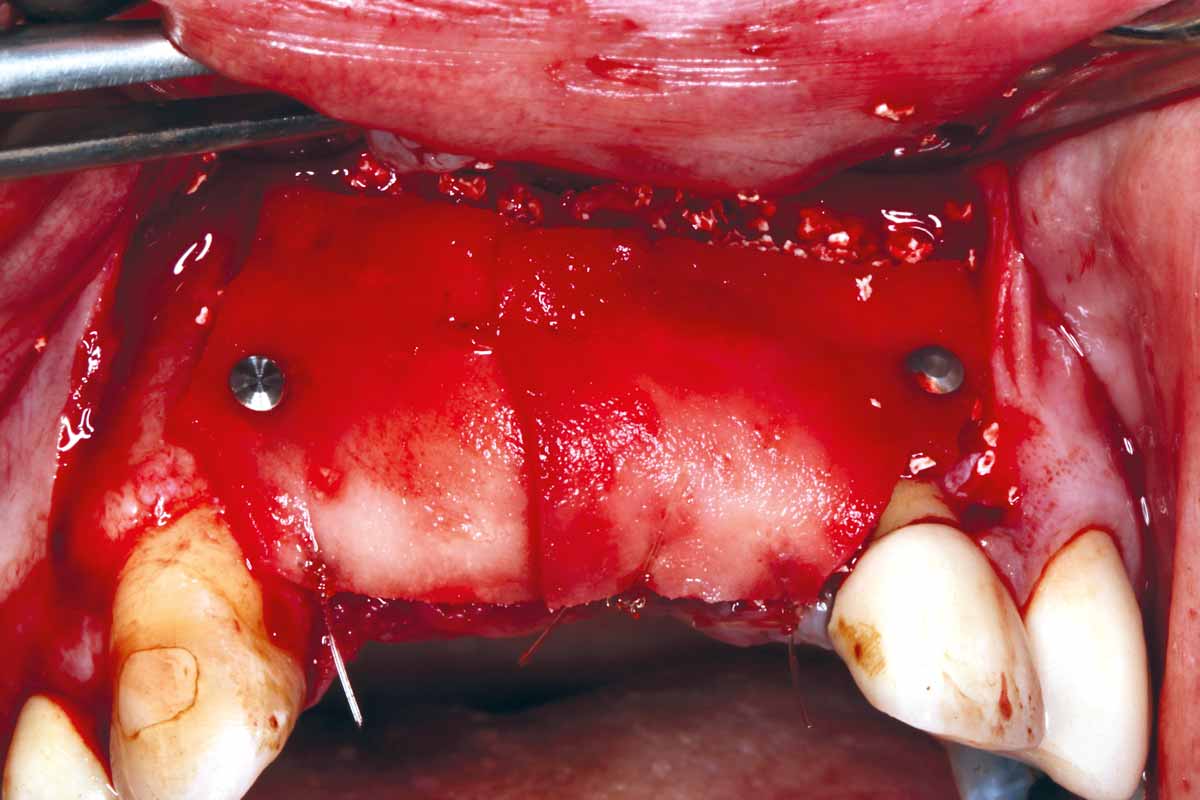

GBR and soft tissue augmentation with cerabone® and mucoderm®

Dr. Hassan Maghaireh – England